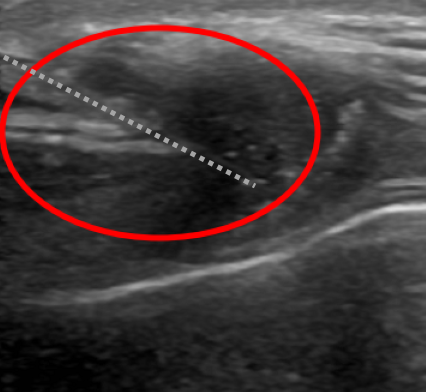

본원에서 갑상선세침흡인세포검사로 진단받은 갑상선암의 증례가 간혹 이어지는 목 이물감으로 인해 본원에 내원하신 30대 남성이었습니다.갑상선 초음파를 저희 병원에서 시행하였습니다.

갑상선의 좌우로 연결하는 잘록한 부위에 1.3센티미터 정도의 결절이 관찰되었습니다. 결절 내부에 석회 부분도 함께 세침 흡인 세포 검사를 실시했습니다.

붉은 동그라미 안에 보이는 점선 위에 보이는 반짝반짝한 물체가 바늘이 갑상선 결절을 통과한 모습입니다 바늘을 이용하여 갑상선 결절에서 세포를 흡인하였습니다.

조직 검사 결과 악성 세포가 의심되었습니다.

결과를 확인한 후 상급병원에 의뢰하여 현재 수술 예정입니다.